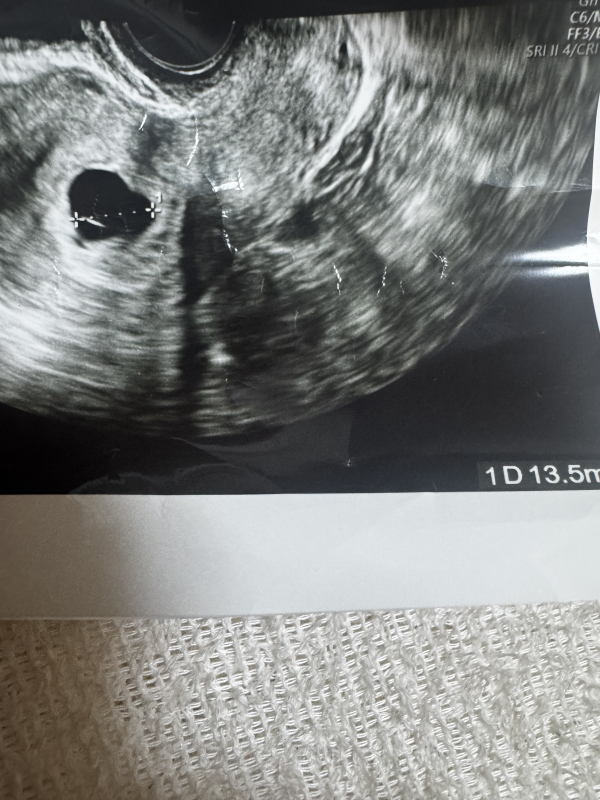

6w4dのエコーです。胎嚢しか見えませんでした。中の白い線はなんでしょうか?

2年ぶりに授かり、1/24に初診に行ったところ、胎嚢13.5ミリしか見えず、胎芽も卵黄嚢も見えませんでした。

胎嚢の中にある白い線はなんでしょうか?

また、右下にぼやけた影があるのは赤ちゃんではないのでしょうか?